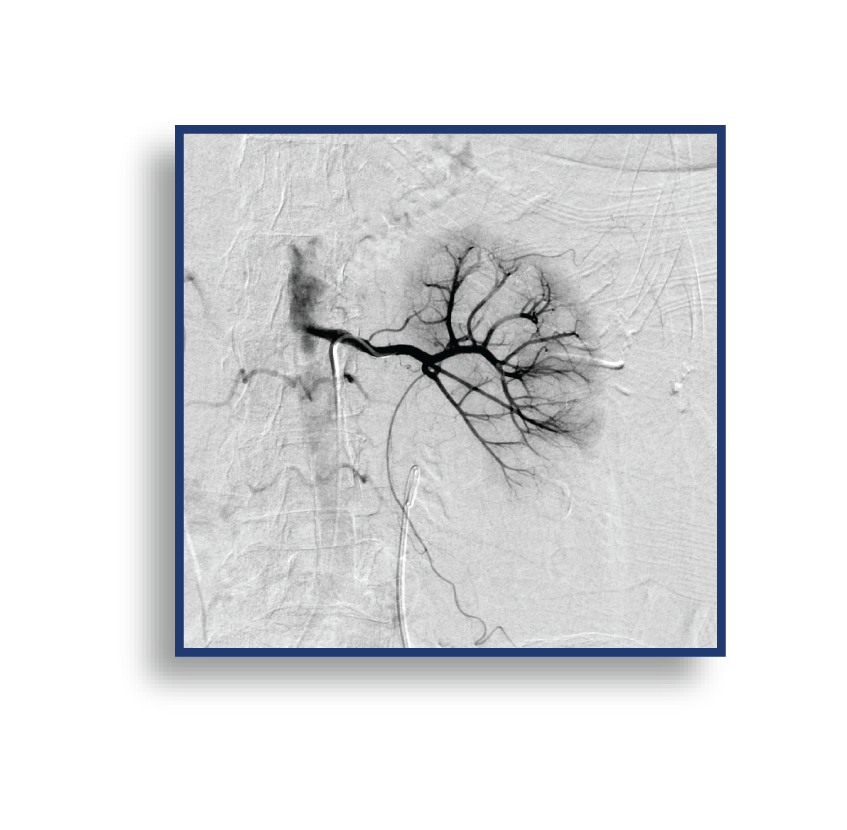

The LAVA Liquid Embolic System (LES) is The First and Only Liquid Embolic Approved for Peripheral Vasculature Hemorrhage.

LAVA provides the confidence to quickly stop bleeds results in controlled target vessel occlusion.

LAVA is available in a 2 mL vial and a 6 mL vial; both vials have an 18 or 34 viscosity option. These pre-mixed vials allow for both a proximal target embolization and a distal target embolization, providing options to reach the bleed. The 2 mL LAVA LES comes with two (2) 1 mL delivery syringes and the 6 mL LAVA LES offers six (6) 1 mL delivery syringes, enabling you multi-zone embolization options from 1 pre-mixed vial. An optional Mixing Kit is available to expedite the shaking of the vial, which suspends the radiopaque particles. The volume of the particles in LAVA has been designed to reduce flash for clear imaging.